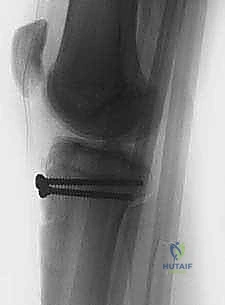

5. التثبيت الداخلي (Internal Fixation)

هنا تبرز مهارة الجراح في اختيار طريقة التثبيت التي لا تضر بصفيحة النمو (إذا كانت لا تزال مفتوحة).

* استخدام البراغي المجوفة (Cannulated Screws): يتم إدخال سلك توجيهي رفيع أولاً، وبعد التأكد من موقعه بالأشعة السينية داخل غرفة العمليات، يتم إدخال برغي أو برغيين من التيتانيوم القوي فوق السلك لتثبيت العظم. يحرص الدكتور هطيف على توجيه البراغي من الأمام إلى الخلف، وفي بعض الأحيان بزاوية مائلة لتجنب اختراق صفيحة النمو قدر الإمكان.

* شريط التوتر السلكي (Tension Band Wiring): في بعض الحالات التي يكون فيها الكسر مفتتاً أو القطعة العظمية صغيرة جداً، قد تُستخدم أسلاك معدنية قوية تُلف حول البراغي ووتر الرضفة لتوفير ضغط ديناميكي يساعد على الالتئام السريع.

بعد التأكد من قوة التثبيت عن طريق ثني وفرد ركبة المريض على طاولة العمليات، يتم غسل الجرح جيداً وإغلاقه في طبقات. تُوضع الساق في دعامة ركبة مفصلية (Hinged Knee Brace) مقفلة في وضع الاستقامة التامة لحماية الإصلاح الجراحي.